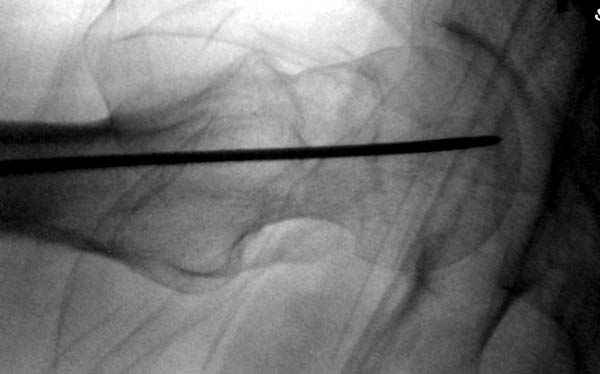

Re: неполный перелом шейки

Профилактику дальнейшего раскола неполного перелома шейки провели тремя канюлированными шурупами.